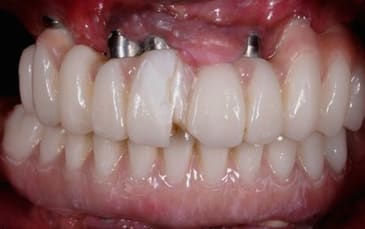

Z'etes pas sympa... surement parce que vous êtes jaloux d'avoir perdu un client comme moi au profit de dtxia !!! Je vous poste une photo et une radio des prothèses... seulement 14000 euros ça m'a couté !! En 3 rdv d'une heure en plus !! Je suis ravi !!

bien sur que non , pour prendre une si belle photo ,il faut un flash annulaire des ecarteurs etc ....

or dentexia ou autre ne peut delivrer une si belle photo qui est un cas d'ecole sans copyright .

ou alors il a volé la photo dans un congrés à un suédois ....